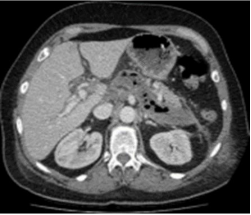

FHC, sexo masculino, 53 anos, na terceira semana de tratamento de pancreatite aguda, realizou a TC de abdome a seguir.

Fonte: Ultimate radiology: acute necrotizing pancreatitis. Disponível em: ultimate-radiology.blogspot.com. Acesso em: 20 ago. 2024.

Qual complicação pode ser identificada na TC?